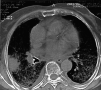

Fig. 4. Tomografía axial computarizada sin contraste. Corte sobre carina traqueal. Patrón difuso reticulonodular y derrame pleural parietobasal bilateral.